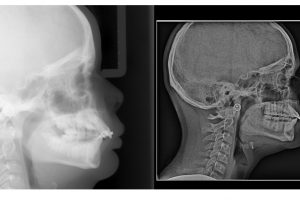

Posted by Lenk Orthodontics on Thursday, January 28, 2021 Lenk Orthodontics isn’t just about teeth: OUR FOCUS IS THE SMILE, BITE, AND OVERALL ESTHETICS…. LOOK AT THE DIFFERENECES IN THIS …

Another great example of why early detection is important!!! Early detection prevented damage to roots, prevented the extraction of teeth, and prevented the need for surgical intervention!! The lower …